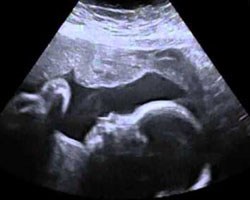

A cara do pequeno afina-se e, na ecografia, já são de todo visíveis as sobrancelhas e a unhas das mãos e dos pés.

Alucinante! Mostramos-te um vídeo e uma ecografia desta 26ª semana. Assim, podes fazer uma ideia de como é o teu bebé nesta semana e quais os movimentos que realiza no interior da tua barriga. Não percas!

Ecografia de 26 semanas